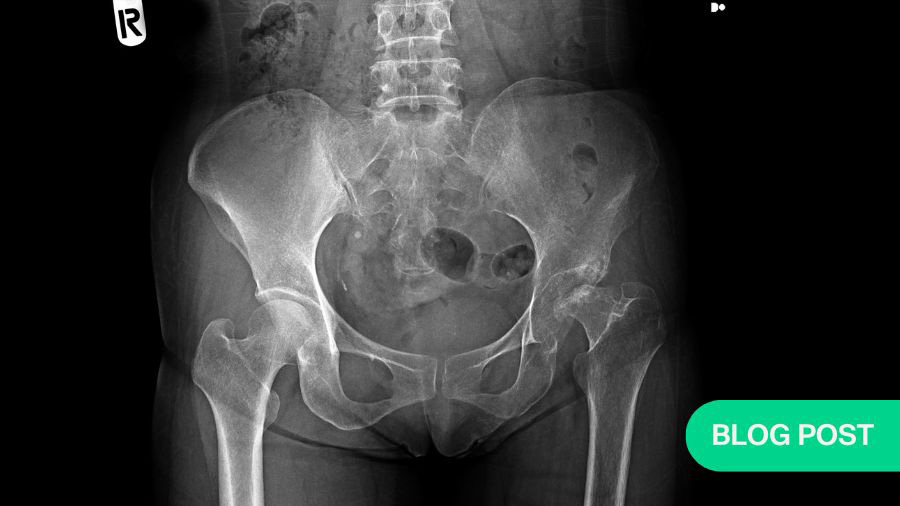

Operative vs non-operative management of geriatric acetabular fractures: persisting clinical challenges in decision-making and outcome reporting

Geriatric acetabular fractures (GAFs) have become an increasingly familiar problem for practicing orthopedic trauma surgeons. Once considered relatively uncommon, these injuries are now encountered with growing frequency as life expectancy increases, and older adults maintain active, independent lifestyles well into advanced age. Unlike hip fractures of the proximal femur, which are managed along well-established treatment pathways, acetabular fractures in elderly patients retain much of the biological and mechanical complexity seen in younger individuals. What changes is the host in which these fractures occur: osteoporotic bone, limited physiologic reserve, multiple medical comorbidities, and heightened vulnerability to complications.

In real-world practice, treatment selection for GAFs is rarely dictated by the fracture pattern alone. Instead, surgeons must integrate multiple layers of information before committing to a course of action. Patient-related variables such as age, baseline mobility, cardiopulmonary reserve, frailty burden, and cognitive status weigh heavily in the decision process. At the same time, fracture-specific considerations—including displacement, comminution, dome impaction, posterior wall involvement, and the presence of associated pelvic injuries—directly influence both the technical feasibility of fixation and the likelihood of durable joint preservation.